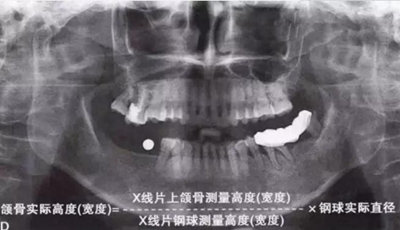

如何通過(guò)曲面斷層片測(cè)量出相對(duì)準(zhǔn)確的數(shù)據(jù)?告訴大家一個(gè)很實(shí)用的方法,就是利用小剛球作為參照。

將小剛球放到口內(nèi)時(shí)拍攝曲面斷層片,拍攝后得到的結(jié)果就是這個(gè)樣子的:

5.jpg

因?yàn)樾偳虻闹睆绞枪潭ǖ?,通過(guò)測(cè)量片子上小剛球的直徑,就能算出曲面斷層片的放大率,然后就能算出真實(shí)的骨高度了,這是一個(gè)很不錯(cuò)的方法。